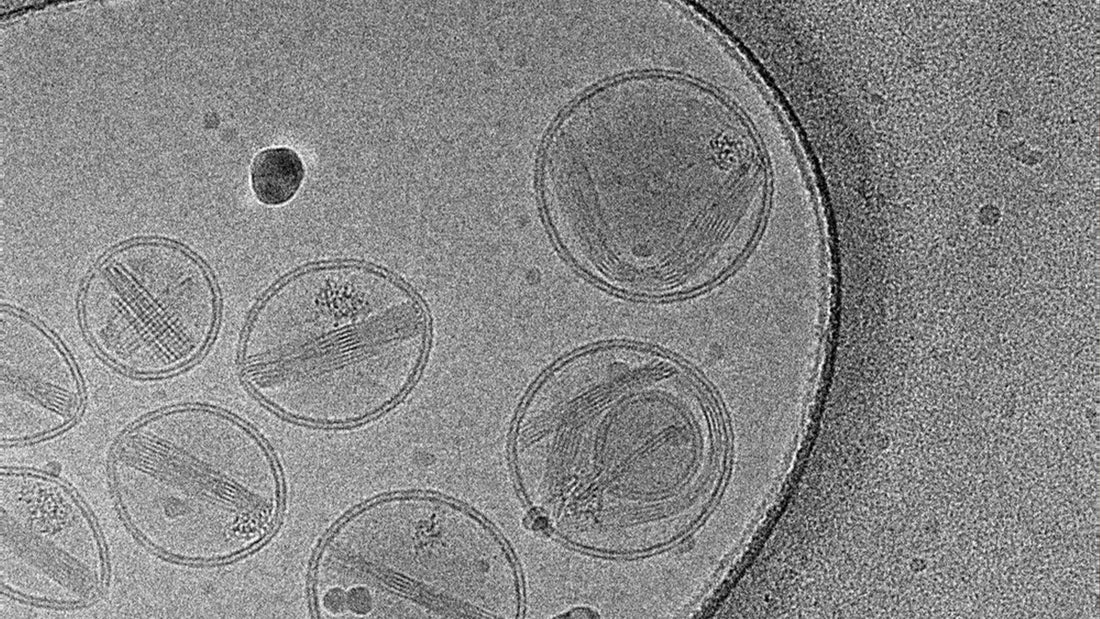

• Lipid nanoparticles (LNPs) in mRNA vaccines facilitate the delivery of mRNA into cells but are not known to cause these side effects directly. Instead, they encapsulate mRNA to protect it until it can be taken up by cells.